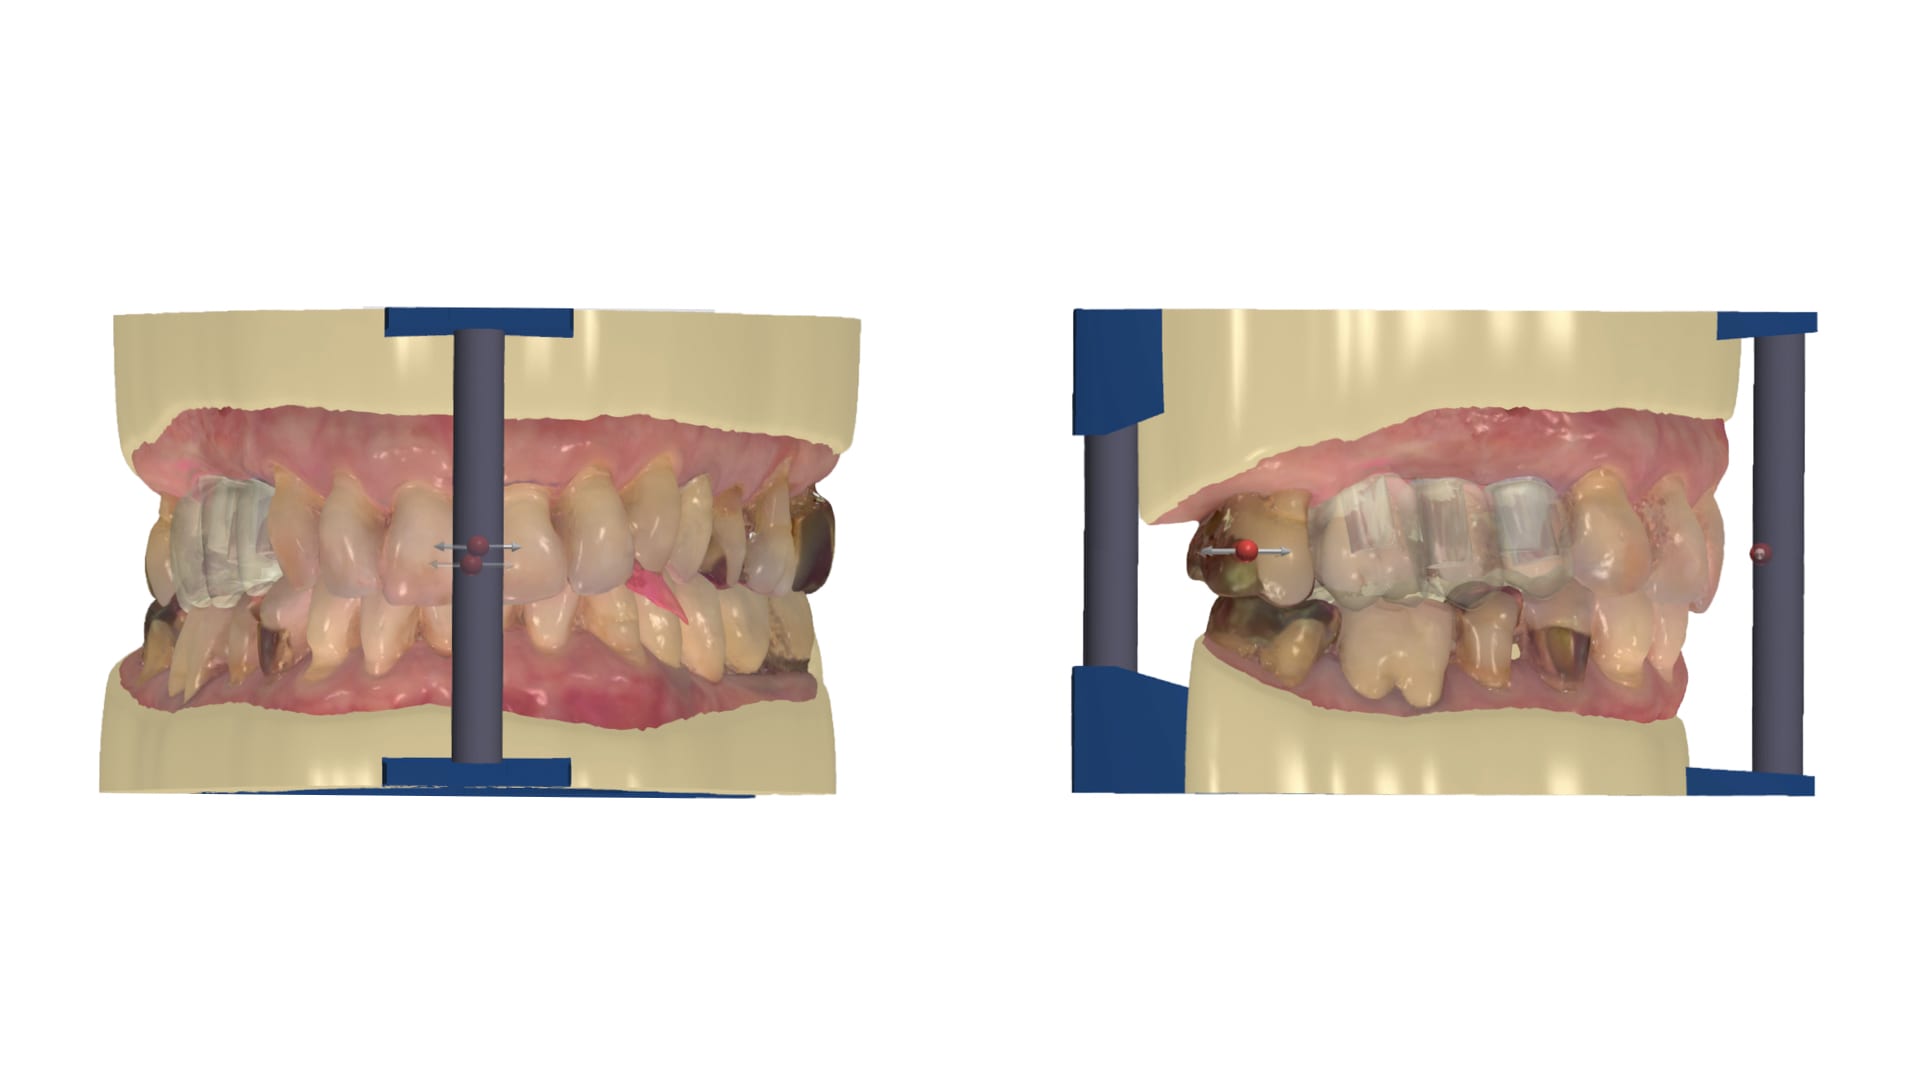

Abb. 4: Intraorale Scandaten in Okklusion

Der Workflow ergibt sich aus der Programmierung. Als erster Schritt erfolgt die Datenbereinigung. Hierbei entfernt der Techniker nicht-relevante Bereiche des Scans sowie mögliche Artefakte. (Abb. 5 und 6) Er richtet die Scans im virtuellen Artikulator ein und legt somit bereits den Grundstein für die folgende digitale Modellverarbeitung (Abb. 7). Im folgenden Schritt werden die mit dem 3Shape Trios 3 intraoral erfassten Scanmarker mit den in der Dental Designer Software hinterlegten DME-Dateien registriert. Hierbei ist besondere Präzision gefordert. Wird der Scanmarker nicht präzise registriert, ist die virtuelle Implantatposition nicht richtig dargestellt und die gefertigte Prothetik wird nicht passen. Softwareseitig stehen dem Nutzer zwei Arten der Registrierung zur Verfügung: die Ein-Punkt- und die Drei- Punkt-Registrierung. Je nach eingesetztem Scanmarker erweist sich die eine oder andere Variante als vorteilhafter. In dem gezeigten Fall erfolgte die Registrierung im Drei-Punkt-Verfahren. Die Software erzeugt im Anschluss automatisch die hinterlegten Datensätze der Modellanaloge und die in der Auftragsanlage ausgewählten Abutmentgeometrien in ihrer jeweilig korrekten Position. Die Ausformung des Emergenzprofils sowie die finale Gestaltung der Abutments werden im Dental Designer mittels Backward-Planning erstellt, das heißt, die zu versorgenden Zähne werden im ersten Schritt vollanatomisch in ihrer finalen Form und Ausdehnung modelliert. Danach arbeitet der Zahntechniker „rückwärts“ und erzeugt so die optimalen Abutments in Abhängigkeit des digitalen Wax-ups sowie die exakt reduzierten Zirkonoxid-Gerüste.